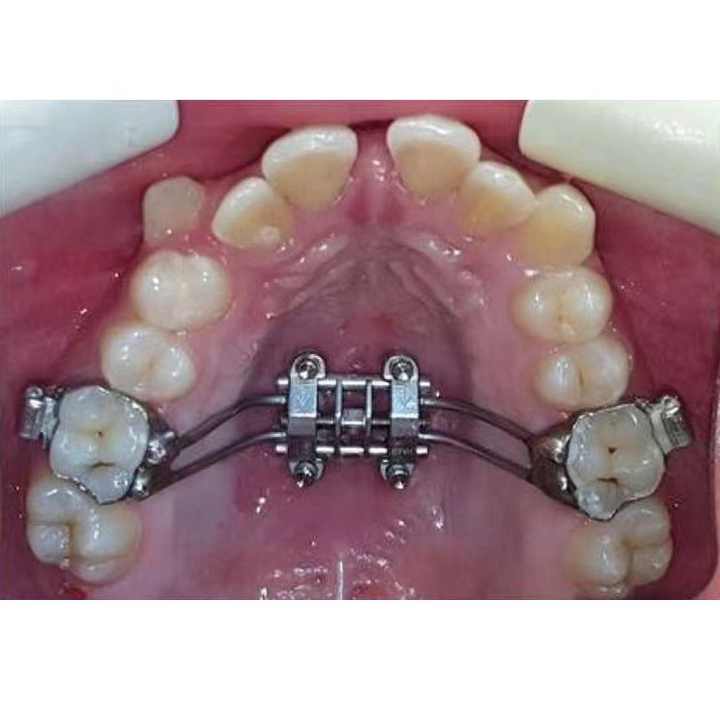

目立ちにくいワイヤー矯正治療|東京三鷹の三鷹miki矯正歯科, 歯科矯正器具ミニ拡張ネジMARPE Rapid Palatal Expander,

歯科矯正器具ミニ拡張ネジMARPE Rapid Palatal Expander,![Amazon.co.jp: お口の専門店(R) [歯科医院取扱品] 歯科矯正用 Amazon.co.jp: お口の専門店(R) [歯科医院取扱品] 歯科矯正用](https://m.media-amazon.com/images/I/714-KCXnNGL.jpg) Amazon.co.jp: お口の専門店(R) [歯科医院取扱品] 歯科矯正用,